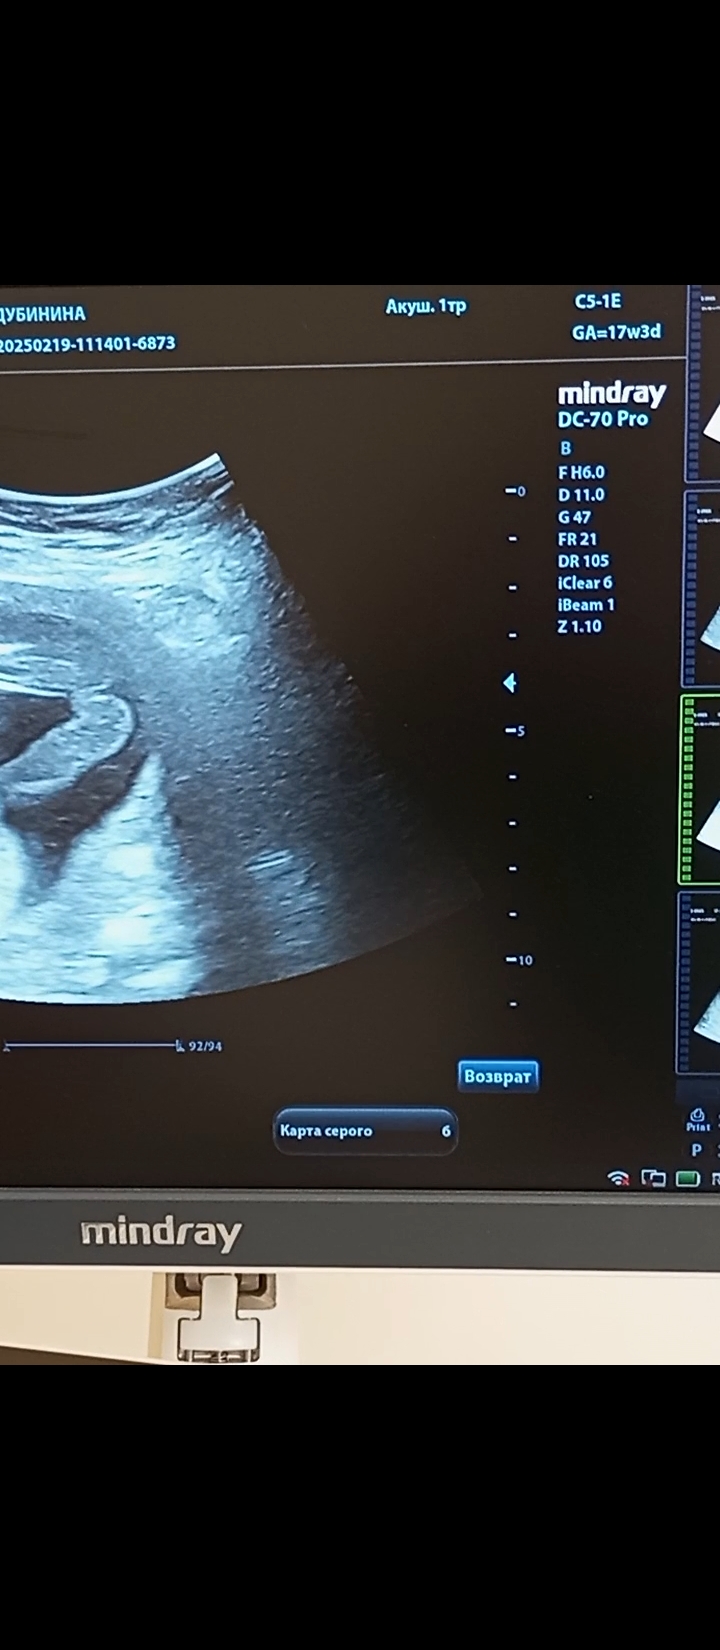

Юлия Мать Драконов, Изображениефото 17 недель.

04.03.2025

А где что на фото? Не понятно что-то 🤔

Не вижу писюна вроде)

Валентина, с пуповиной врач не могла перепутать? на этот фото явно девчачий пирожочек